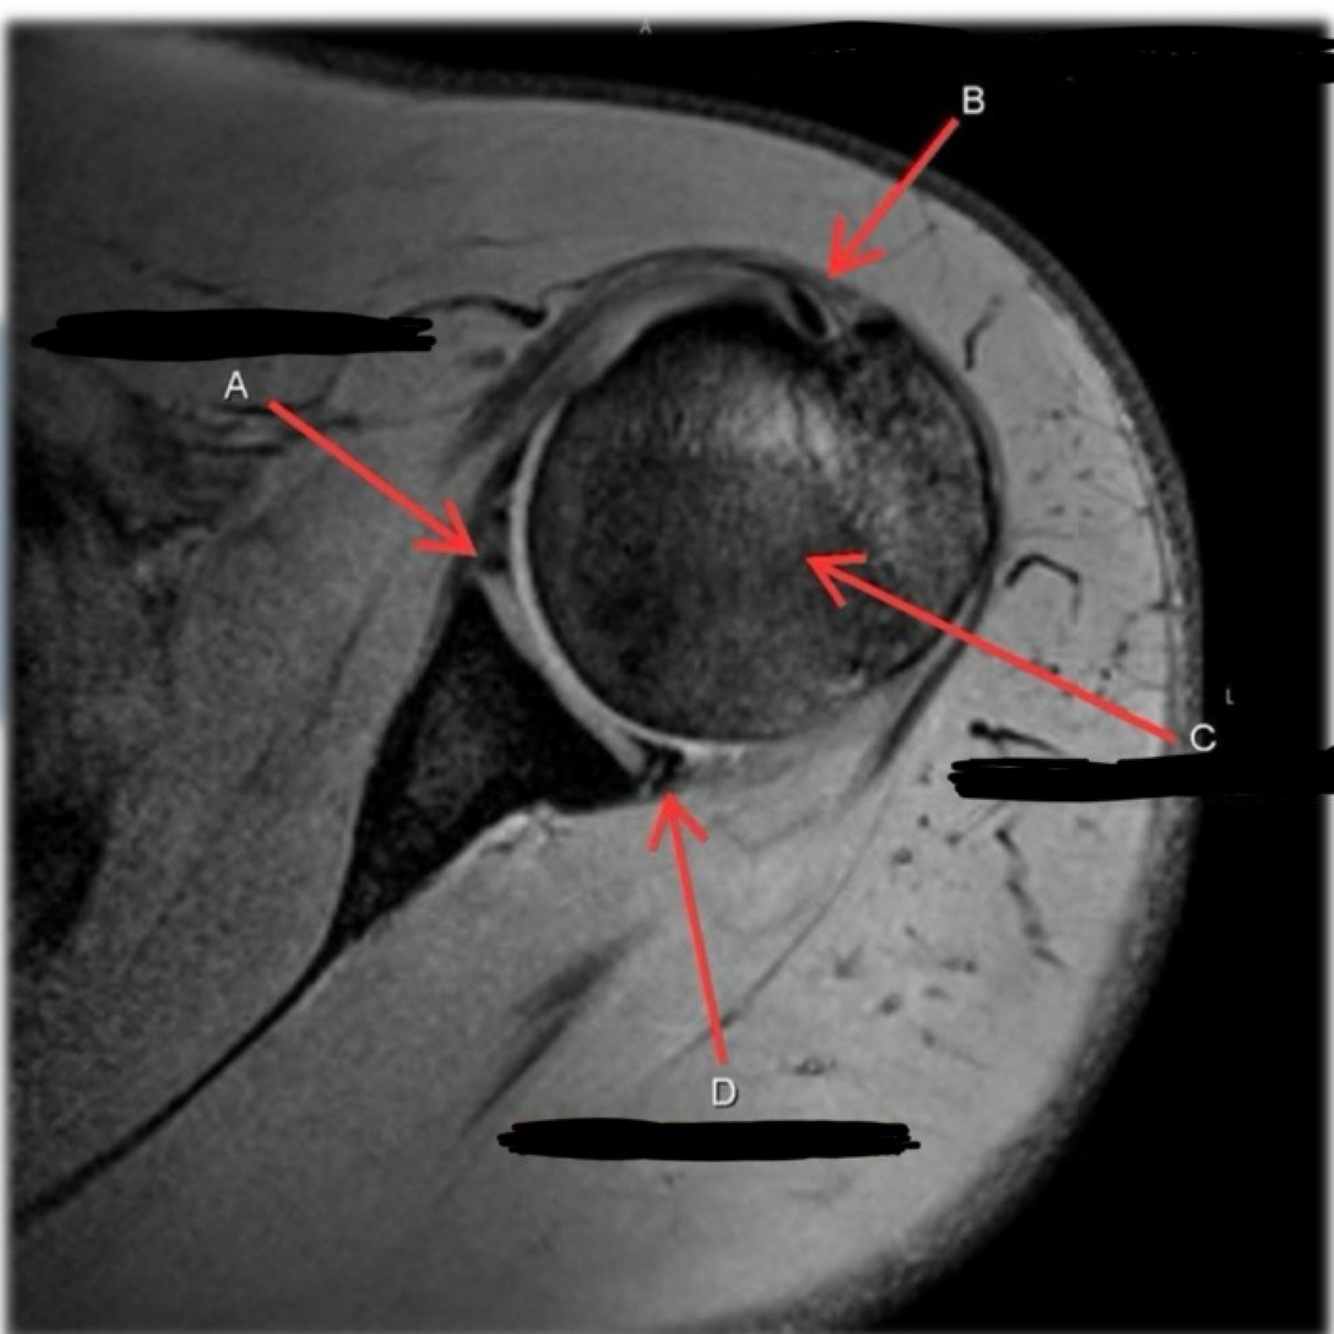

11

Q

What is letter A?

A

ANTERIOR LABRUM

How well did you know this?

1

Not at all

2

3

4

5

Perfectly

12

What is letter B?

BICEPS TENDON (LONG HEAD)

13

What is letter C?

HEAD OF HUMERUS

14

What is letter D?

POSTERIOR LABRUM